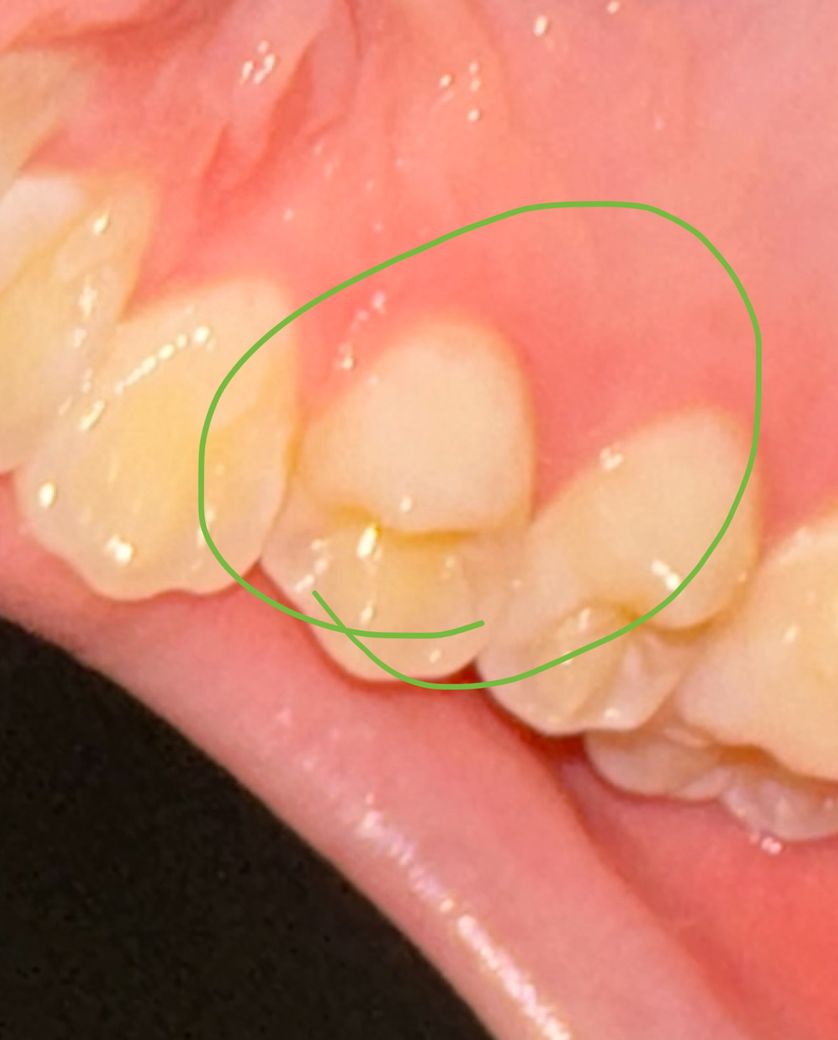

사진 속 치아가 압력이 가해지면 아픈데 치은염인가요?

음식먹을때 저기로 압력이 가해지면 아프고요 가만히있으면 안 아파요

근데 아픈 것도 엄청 아픈 게 아니라 그냥 거슬리는정도예요

찬 물이나 뜨거운 물에 반응하지는 않고요

단 음식 먹는다고 아픈 것도 아니에요

잇몸이 약간 붉어보이는데 치은염인가요?

현재 치과를 못 가는 상황인데 집에서 최대한 할 수 있는 조치가 무엇인가요?

사진으로 봤을 경우에는 큰 문제는 없어 보입니다. 치아에 가해지는 힘이 강하다면 치아에 일시적으로 통증이 있을 수 있습니다. 치아에 가해지는 힘을 줄여 보시고 그래도 통증이 지속된다면 치과에서 진료를 받아보는 것을 권유 드립니다.

증상만으로는 진단은 어렵습니다만 치은염 가능성은 높겠습니다. 치은염은 칫솔질을 꼼꼼하게 열심히 하고 치실을 사용함으로써 건강한 잇몸을 회복할 수 있습니다

잇몸에 염증이 있는 초기 단계로 보이며, 우선은 해당부위를 부드러운 칫솔모로 꼼꼼히 양치하여 관리하여 보고, 만약 통증 및 불편감이 지속시에는 치과에 방문하여 검진을 받고 스케일링 치료를 받길 권합니다.